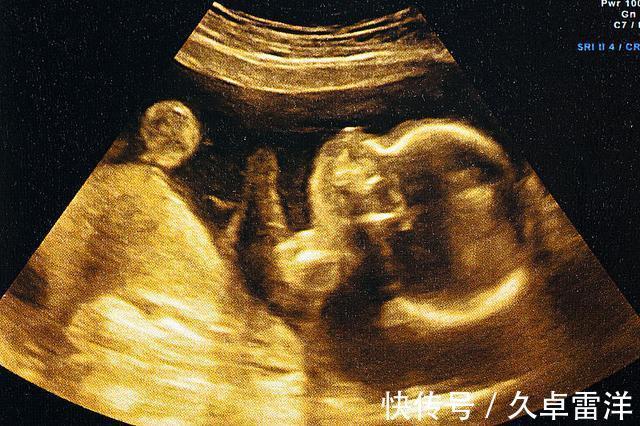

2、B超技术尚不完善别看现在B超使用率很高,感觉技术相当成熟的样子,其实行内人都知道,它的问题极多,比如最关键的一条:成像模糊。B超的工作原理是声波与光波技术结合而成,通过特殊的算法,将这些检测手段反馈的数据进行分析,最后形成图形供给医生诊断。然而,由于技术上的限制,该算法尚未完善,因此,最终的成像结果也达不到清晰可见的程度,医生在诊断时,大部分判断依靠专业知识,而剩下的只能靠经验以及感觉。